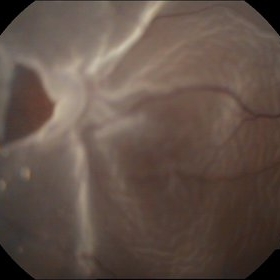

Traumatic Optic Nerve Avulsion

Jul 16 2015 by Mehul A Shah

A 21-year-old male presented to outdoor with history of blunt trauma and loss of vision on examination we found anterior segment to be normal and posterior segment had this picture.

Photographer: Mehul Shah, Drashti Netralaya

Imaging device: FF450 plus zeiss

Condition/keywords: blunt trauma, optic neuropathy